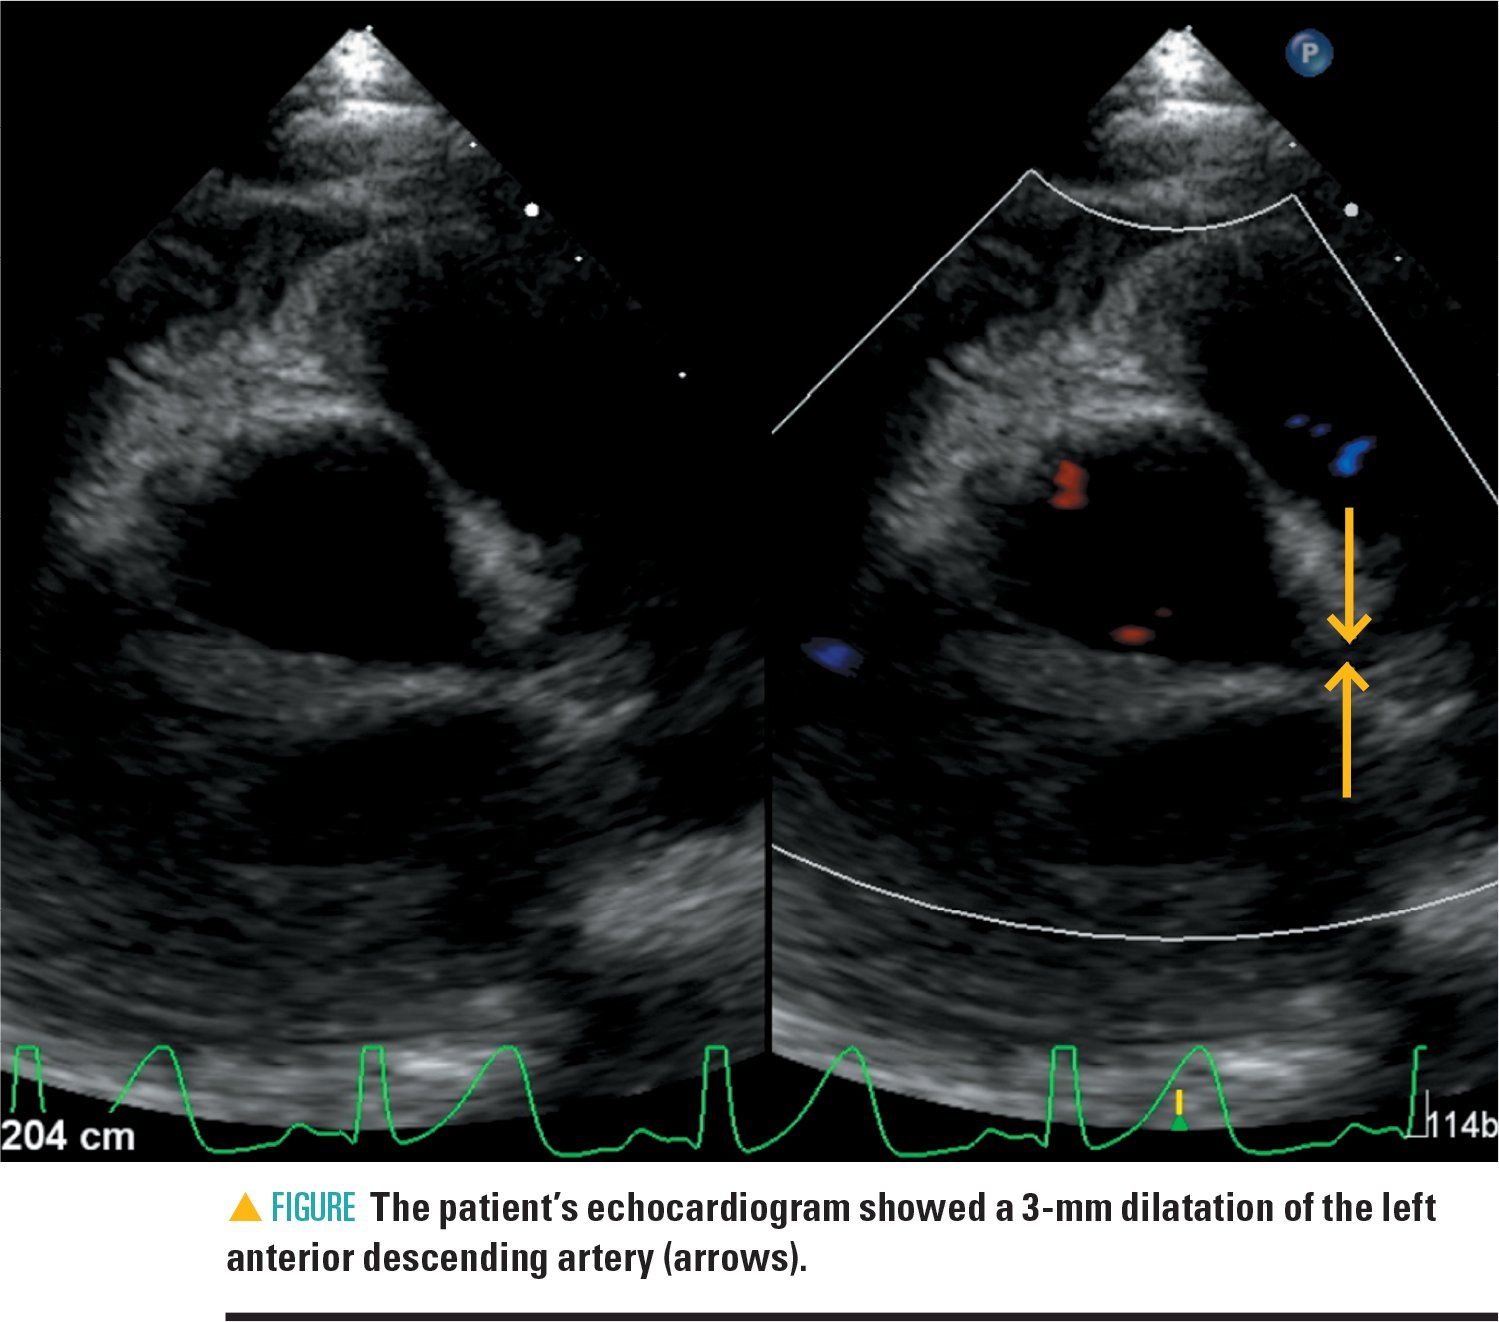

The day after discharge, the patient again began complaining of abdominal pain. He also developed a fever of 101°F and conjunctival injection, so his family returned to the ED. Laboratories at that time were remarkable for an elevated CRP (from 4.79 on his discharge day to 5.68) but stable liver function tests. He was given a second dose of IVIG and restarted on high-dose aspirin. A repeat ECHO showed a 3-mm dilatation of the left anterior descending artery (Figure).

Although this patient did not manifest gall bladder disease specifically, he did have hepatobiliary disease and developed coronary artery dilatation and impaired IVIG responsiveness. His long-term prognosis is worrisome for early coronary artery disease and he will require monitoring throughout his life.